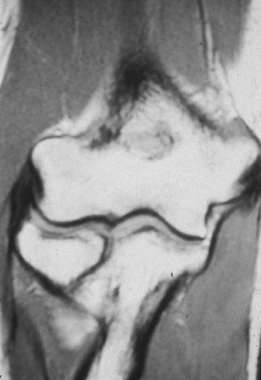

Unfortunately, the magnetic resonance imaging (MRI) scan is not always

capable of delineating the difference between degenerative tendinitis

that is otherwise asymptomatic, and symptomatic tendinitis or a tear

with associated laxity. An MRI scan revealing a normal ulnar collateral

ligament (Fig. 81.7) can provide impetus to search for a different diagnosis. Arthrography is not useful

because of frequent false negative findings in cases of chronic ulnar collateral ligament insufficiency with an intact capsule.